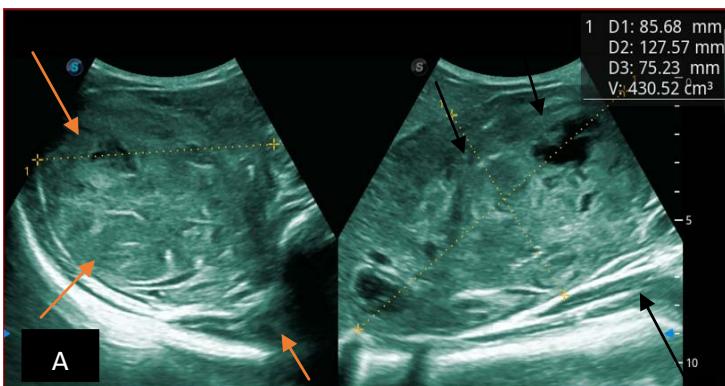

Figure 5: Abdominopelvic ultrasound control after 6 courses of chemotherapy in the same 3 year old patient with a ruptured left renal nephroblastoma; Images A, F, G, and H: show regression of the solid, endo and exo renal, left nephroblastoma mass treated with 6 courses of chemotherapy (current volume 430 ml vs) Images: B, C, and: show persistence of thrombotic permeation pan vena cava and ipsilateral renal. Image E: shows a volumetric regression of the intra-lesional hematic collection, at the tumor rupture estimated at 34.49 ml VS, Image I: represents the right kidney in B mode which is of normal echoculture. Source: Dr. Frederick Tshibasu Tshienda database.